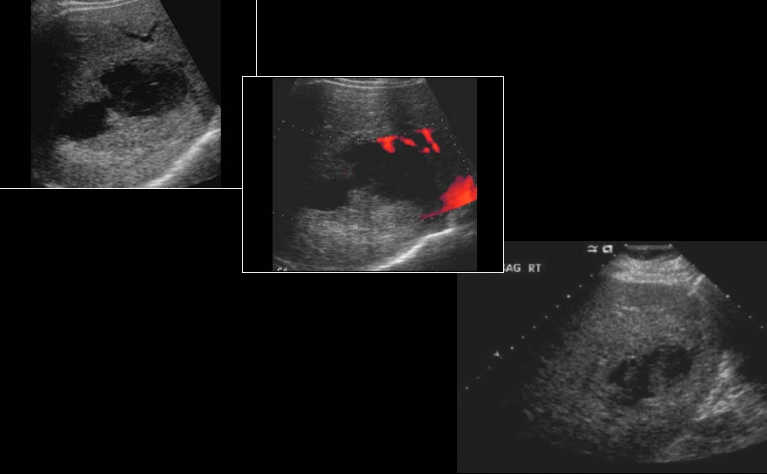

hepatic candidiasis

(most commonly) pneumocystis carinii (associated with hepatic granuloma)

hepatic granulomas (associated with pneumocystis carinii)

hepatocellular carcinoma (HCC)